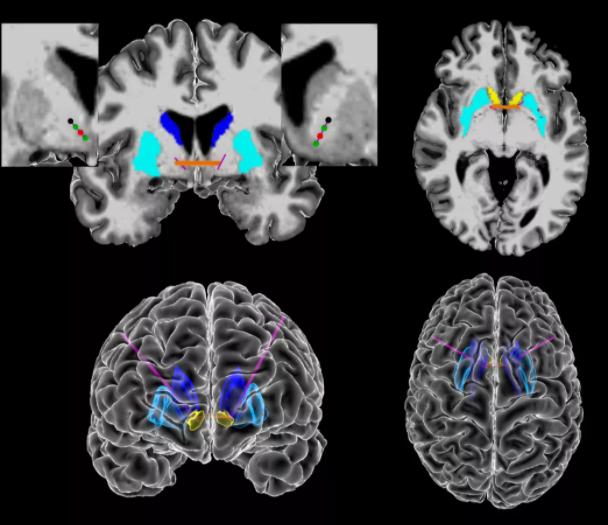

我们可能了解过到的严重强迫症常用的治疗方式,就是心理干预与药物治疗。心理干预与药物治疗是惯常的方式,但对于一些强迫症患者来说,这类治疗方式并没有什么作用。这类人群开始向深部脑刺激的治疗方式投去目光。深部脑刺激可以起到非常好的疗效,超过一半的强迫症患者症状明显改善,生活质量显著提高。不过对于部分强迫症患者的症状疗效治疗效果也不太理想,但是其焦虑、抑郁等伴随症状均明显改善。

深部脑刺激的方式对于一些心理疾病的治疗具有不错的反馈效果,但是在治疗的过程中,深部脑刺激的频率与强度都是跟医生的经验相关,这也意味着这类治疗手段,对于医生的水平以及经验要求较高,具有较大的升级空间。近日,一项有关用AI的研究分析首次识别出了大脑中强迫症相关的脑电波信号,为强迫症的诊断和针对性治疗带来新的增益。

对于强迫症患者来说,深部脑刺激的频率与强度跟医生的经验水平挂钩,疾病的治疗管理非结构化,管理比较复杂,精准刺激深部脑电部位,识别患者强迫症的发作时机成为机器干预的关键环节。

运用AI技术识别大脑中强迫症相关的脑电波信号,针对这一信号调整深度脑刺激强度,为强迫症的针对性与精准治疗打开了新窗。

这个研究团队来自美国布朗大学脑科学研究所,David A.Borton教授带领的研究团队通过对5名重度强迫症患者进行长期脑电监测,经过长期的收集研究与观察,利用人工智能对患者生活中的强迫行为进行分析,评估患者各种微妙的情绪变化,并与脑电波活动相匹配。除了脑电波信号,研究人员还收集了一套强迫症患者行为的生物标志物,包括面部表情和身体运动。通过人工智能,他们发现这些行为和特征与大脑内部信号变化密切相关。

并且,研究人员也用试验证明了,当患者出现这些强迫症状,依据AI给出的深部脑刺激位置,可以显著地改善患者的强迫症状。研究人员也在不断地精进深部脑刺激的系统,向自动化刺激的方向前行。

什么意思呢?就是在患者出现强迫症信号的时候,系统可自动捕捉并及时利用深部脑刺激进行针对性缓解,依据患者症状强度,自动调节刺激强度。目前研究人员计划进一步招募更多患者进行试验,以捕捉更多的强迫症脑电信号标志,丰富自动化深部脑刺激系统的功能。目前研究人员正在开发自动化深部脑刺激系统。